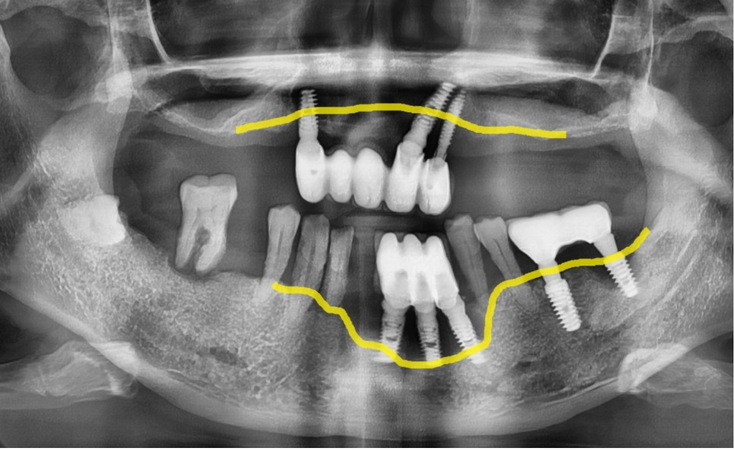

(Ảnh bên dưới) Chúng ta hãy xem kỹ hơn bức ảnh toàn cảnh 3D.

Bạn có thể thấy đường viền nướu vốn đáng ra phải là

đường chấm màu xanh lam nay đã chìm xuống đường

viền màu vàng đậm nằm ở đầu chân răng.

Khi nướu đã tụt đến mức này thì việc răng rụng cũng không có gì lạ,

răng tự nhiên bên cạnh đã ăn sâu vào chân răng nên sẽ rụng sớm thôi.

(Hình bên dưới) Nếu quan sát tình trạng viêm xung quanh trụ implant,

bạn có thể thấy xương nướu ở vùng răng cấy ghép phía dưới đặc biệt bị lõm xuống so với các vùng khác.

(Vạch liền màu vàng là đường xương nướu)

Ngoài ra, xác nhận xương nướu răng hàm trên đã tụt xuống đáng kể, chỉ bằng một nửa so với trụ implant.

Cả hàm trên và dưới đều là những biểu hiện điển hình của viêm quanh implant.